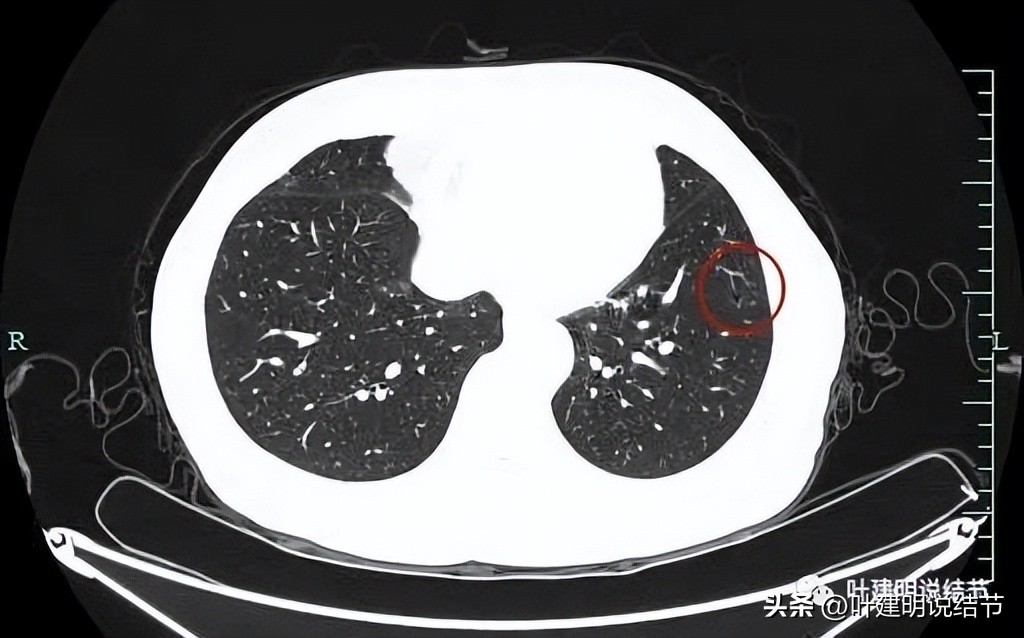

似乎见微小血管走向病灶。

微小血管征确实有。

上图显示了病灶轮廓与瘤肺边界其实还是清楚的。

部分边缘有毛刺征可见。